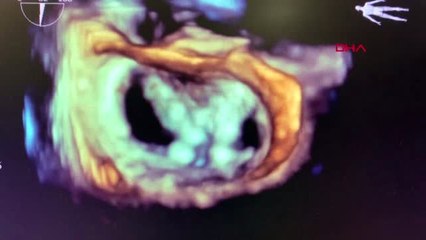

Sivas'ta yaşayan ve 3 aydır yürüme güçlüğü çeken hasta, Eskişehir Şehir Hastanesinde ameliyatla ağrılarından kurtulup sağlığına kavuştu. brbr Evli ve 3 çocuk babası emekli memur Yusuf Çataltepe, kalçasındaki ağrılar nedeniyle Eskişehir'e gelerek Şehir Hastanesine başvurdu. Muayenesinde, Çataltepe'nin kalça ağrılarına eklem sorunlarının neden olduğu belirlendi.br Ortopedi ve Travmatoloji Uzmanı Opr. Dr. Aytek Hüseyin Çeliksöz ve ekibi, Çataltepe'ye kapalı artroskopi ameliyatı uyguladı.br Çeliksöz, gazetecilere, kapalı yöntem ameliyatın bölgede nadiren, Eskişehir Şehir Hastanesinde ise ilk kez yapıldığını söyledi.br Çataltepe'nin durumuna ilişkin bilgi veren Çeliksöz şunları kaydetti: br "Hastamızın kalçasında, kasığına vuran ciddi bir ağrısı vardı. Oturup kalkarken, yürürken şiddetli ağrıları oluyordu, dizini karnına doğru çekemiyordu. Muayenesinde çekilen MR'ında, kalça ekleminde bir problemi olduğunu ve bu problemin kapalı bir kalça artroskopi ameliyatı ile giderebileceğini gördük. Haberabr br hbrlr1.